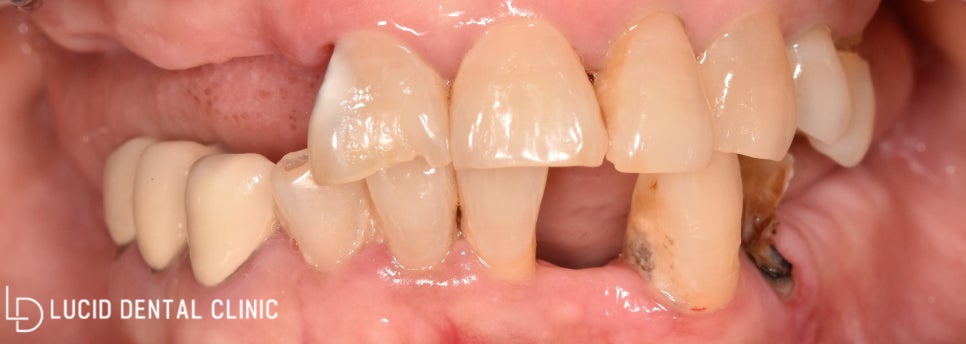

치아 변색뿐만 아니라

정출까지 심하게 나타나

이대로 계속 놔두게 되면

남은 자연치 보존이

어려워질 수 있습니다.

우선 스케일링과 마취로 기본 세팅을 마치고,

문제가 되는 치아 발거를 시작했습니다.

이미 정출이 진행되고 있었기 때문에

큰 어려움 없이 발거에 성공하고,